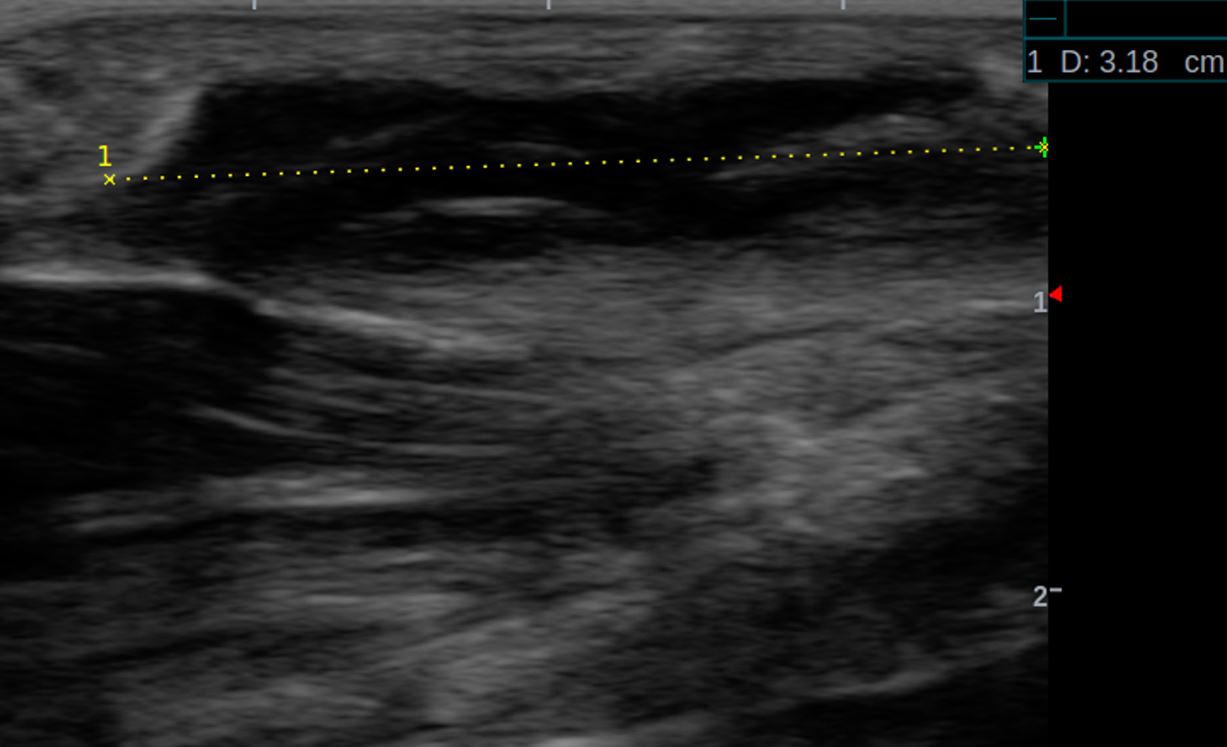

Ledderhose SOno sagital mit Längebestimmung